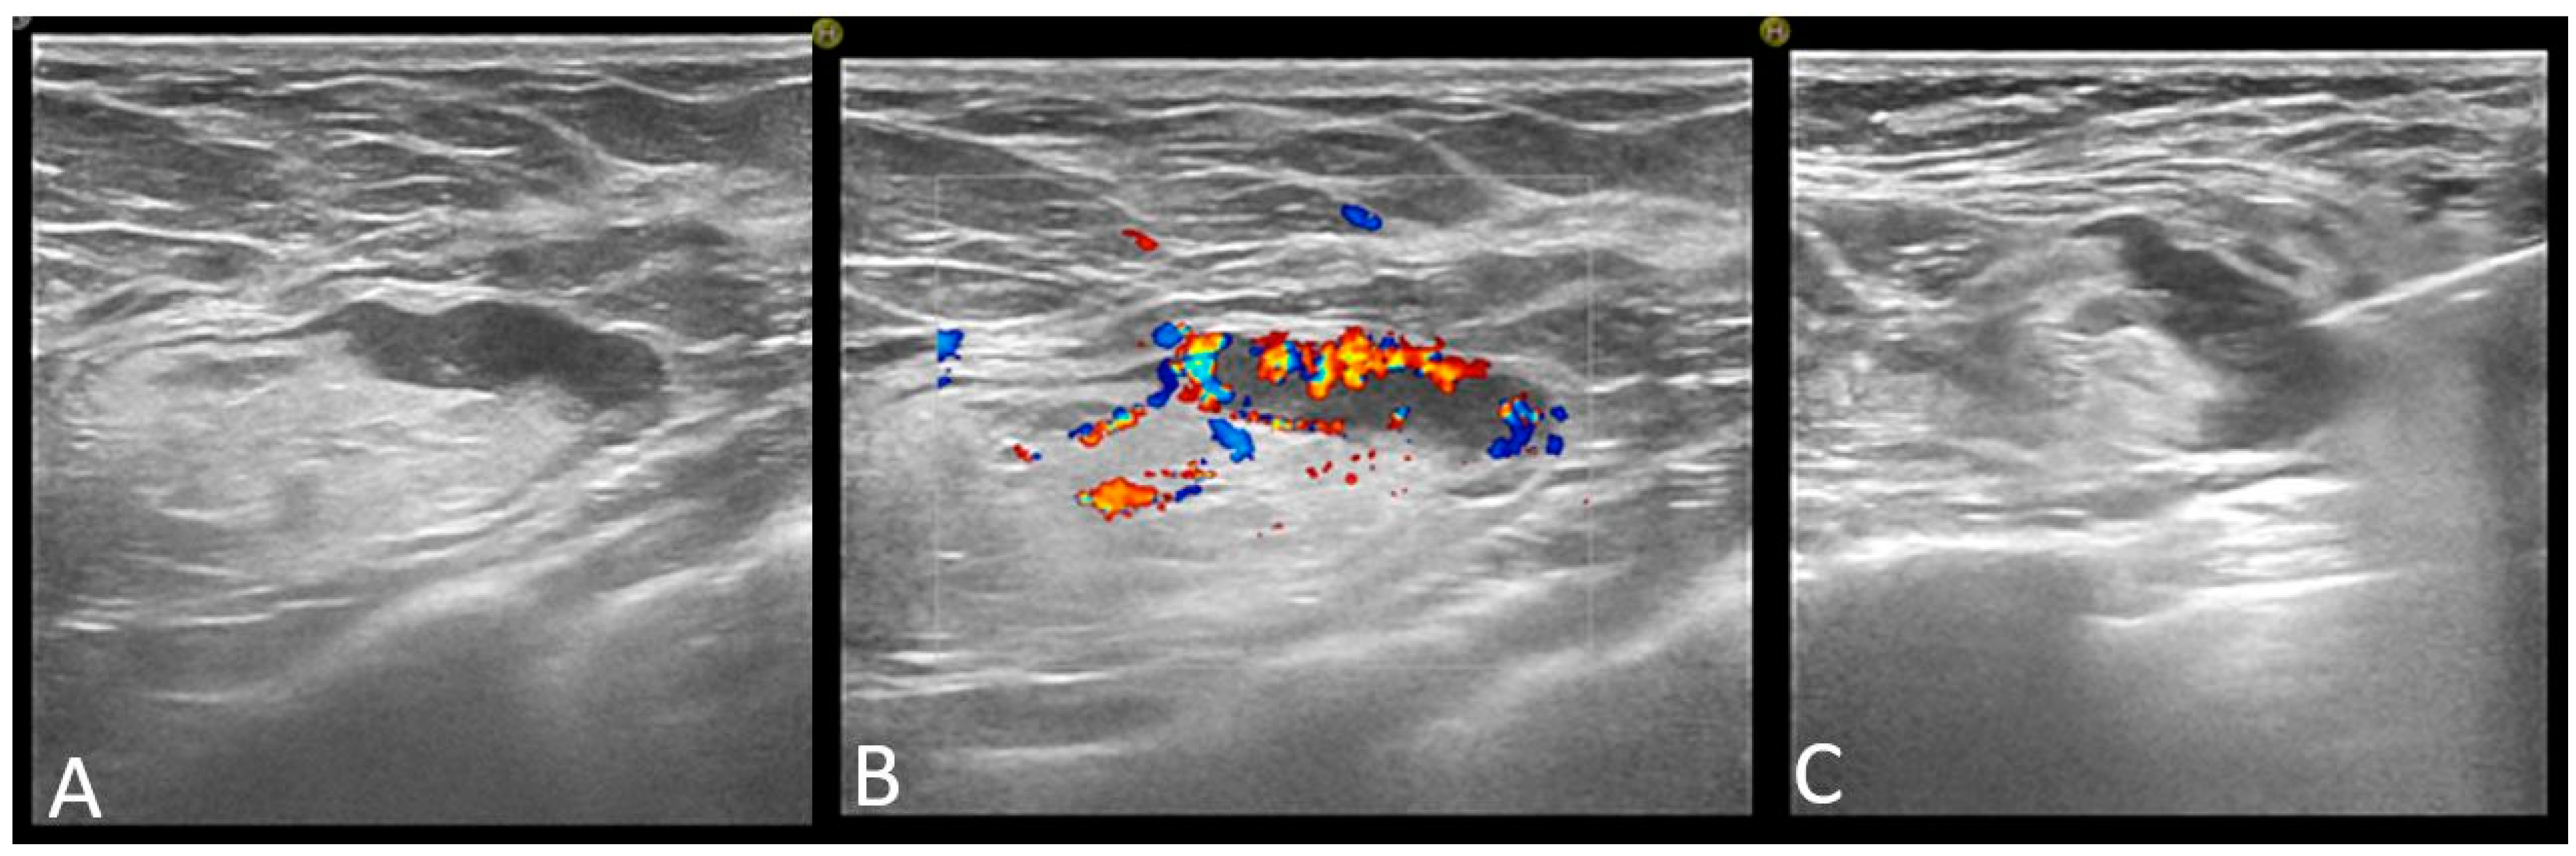

All performed axillary biopsies were US-guided core-needle biopsies. No fine needle aspiration was performed. Figure 4

Figure 4. Axillary lymph node classified as abnormal on ultrasound: focal cortical thickening of more than 3 mm (A) with chaotic vessels (B), and core-needle biopsy was performed (C).